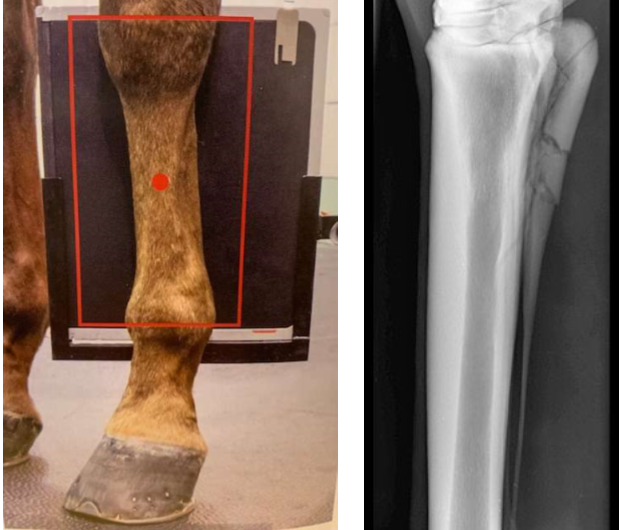

• what image is this?

dorsopalmar of the first phalanx